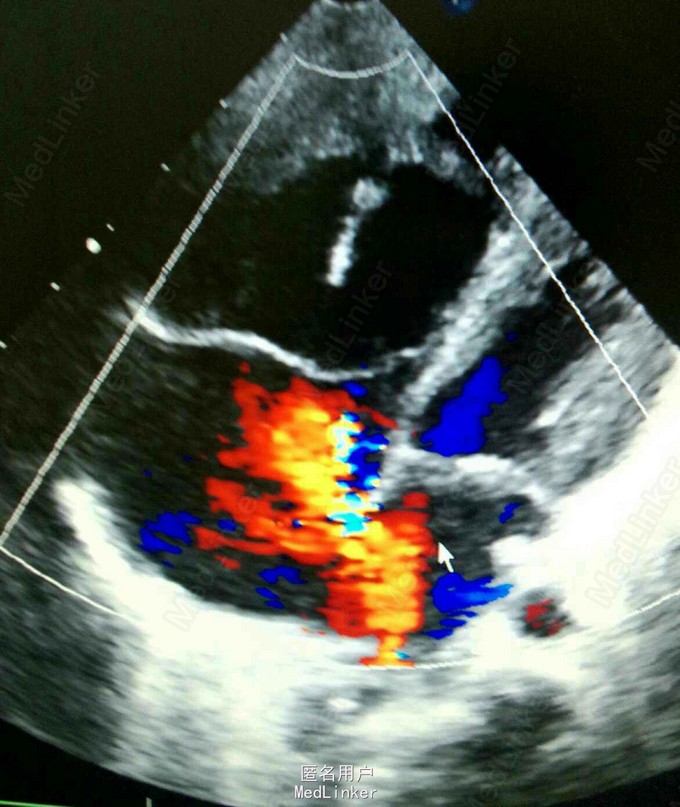

双肺呼吸音粗,可闻及中量哮鸣音及湿罗音。腹部彭隆,肝脾未触及。辅查:B超提示ASD,PDA,三尖瓣轻度反流,肺动脉高压(中度)。血象高,以淋巴为主。

诊断为:高原性心脏病,慢性肺炎,先心。 处理:予小剂量多巴胺强心,利尿。予美洛西林钠舒巴坦钠联合头孢硫脒抗感染治疗。营养心肌,雾化等对症。支气管镜提示喉软骨软化。加用伊可新对症。顺尔宁止咳平喘。患儿咳嗽逐渐好转。